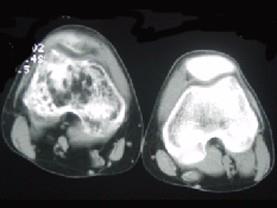

问题 患者女,28岁,右膝跌伤伴疼痛9年,加重及活动障碍1年半,经药物治疗及理疗后病情无好转,既往无特殊病史,查体跛行步态,触痛,请结合所提供的图像,选择最佳选项 ( )

选项 A、软骨肉瘤 B、骨巨细胞瘤 C、滑膜肉瘤 D、骨肉瘤 E、结核

答案 C